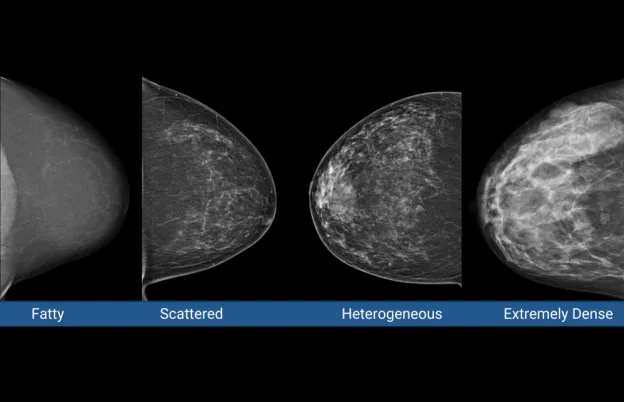

Understanding Dense Breasts: A Guide to Effective Imaging Choices